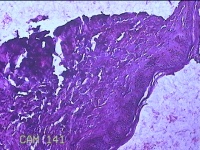

左大腿皮肤肿物

性别

男

年龄

34岁

临床诊断

皮肤感染

一般病史

左大腿麻木十五年。

标本名称

大体所见

灰白粉红色肿物0.7x0.5x0.2cm一个,表面糜烂。

图2